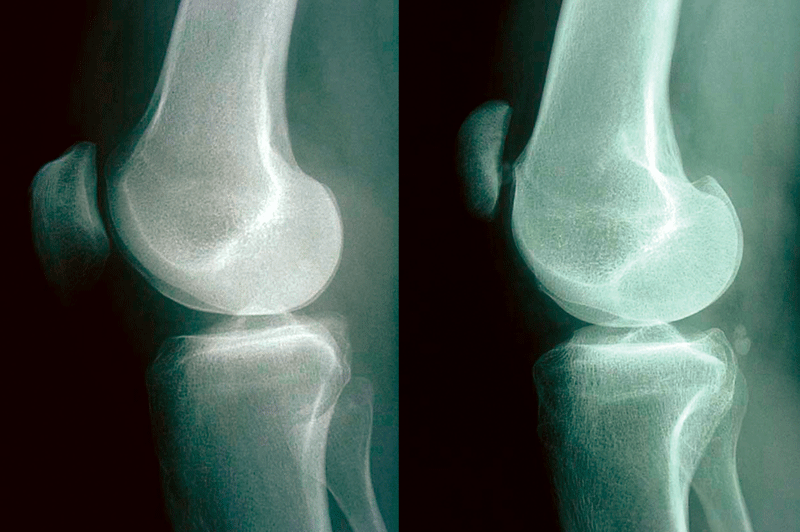

Bei Knieschmerzen kommen viele Ursachen infrage - beispielsweise eine „Gelenkmaus“ (links) oder ein patellofemorales Schmerzsyndrom (rechts). Bei Knieschmerzen kommen viele Ursachen infrage - beispielsweise eine „Gelenkmaus“ (links) oder ein patellofemorales Schmerzsyndrom (rechts). © Jerosch J. internistische praxis 2018; 59: 253-272; © Mediengruppe Oberfranken – Fachverlage GmbH & Co. KG, Kulmbach

Am patello-femoralen Schmerzsyndrom, einer weiteren häufigen Ursache für atraumatische Kniebeschwerden, leiden vor allem jüngere Frauen. Wichtig: Es muss nicht an der Patella liegen, die Beschwerden können auch durch eine Trochleadysplasie, einen Formfehler des Gleitlagers, ausgelöst werden. Neben Schmerzen z.B. beim Treppensteigen müssen Betroffene auch mit einem unerwünschten Nachgeben des Gelenks (Giving-way-Syndrom) rechnen. Als Folge des Ergusses bildet sich eine „tanzende Patella“. Die Therapie erfolgt primär konservativ, wobei das Auftrainieren des M. vastus medialis im Vordergrund steht.

Patellofemorales Schmerzsyndrom mit Trochleadysplasie (Crossing sign, rechts). Zum Vergleich: eine normale Trochlea (links). Patellofemorales Schmerzsyndrom mit Trochleadysplasie (Crossing sign, rechts). Zum Vergleich: eine normale Trochlea (links).